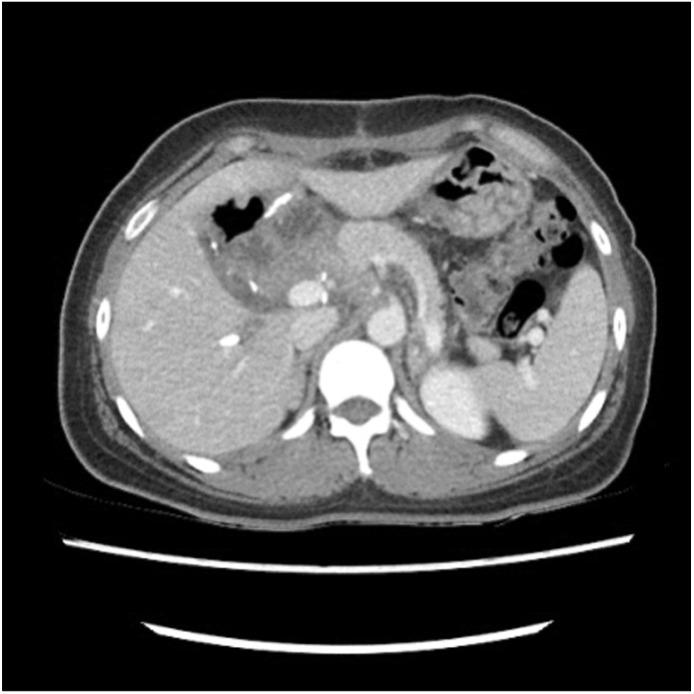

Inflammatory myofibroblastic tumors (IMTs) are a rare chronic inflammatory disease with unclear pathogenesis and pathological features that are not those of a malignant tumor. It is difficult to differentially diagnose them without surgical excision because of their unpredictable clinical behavior, which ranges from benign to locally invasive aggressiveness. We report two cases of IMTs that were diagnosed after surgery. In one case, the IMT originated in peri-splenic area in a 63-year-old female patient. The other case involved a 48-year-old female patient who suffered from an IMT of the head of the pancreas. Both of these cases did not require further treatment based on histological findings, and there has been no evidence of recurrence or metastasis so far. These cases show that the primary choice for the exact diagnosis and proper treatment of IMTs is complete surgical resection.

炎性肌纤维母细胞瘤(IMTs)是一种罕见的慢性炎症性疾病,其发病机制尚不清楚,病理特征也不符合恶性肿瘤的特征。由于其临床行为不可预测,从良性到局部侵袭性,在未进行手术切除的情况下很难进行鉴别诊断。我们报告两例术后诊断为炎性肌纤维母细胞瘤的病例。其中一例,炎性肌纤维母细胞瘤起源于一名63岁女性患者的脾周区域。另一例涉及一名48岁女性患者,她患有胰腺头部的炎性肌纤维母细胞瘤。根据组织学检查结果,这两例均无需进一步治疗,迄今为止也没有复发或转移的证据。这些病例表明,炎性肌纤维母细胞瘤准确诊断和恰当治疗的首要选择是完整的手术切除。